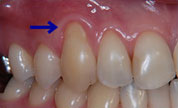

- RETRACTION

- 歯肉退縮